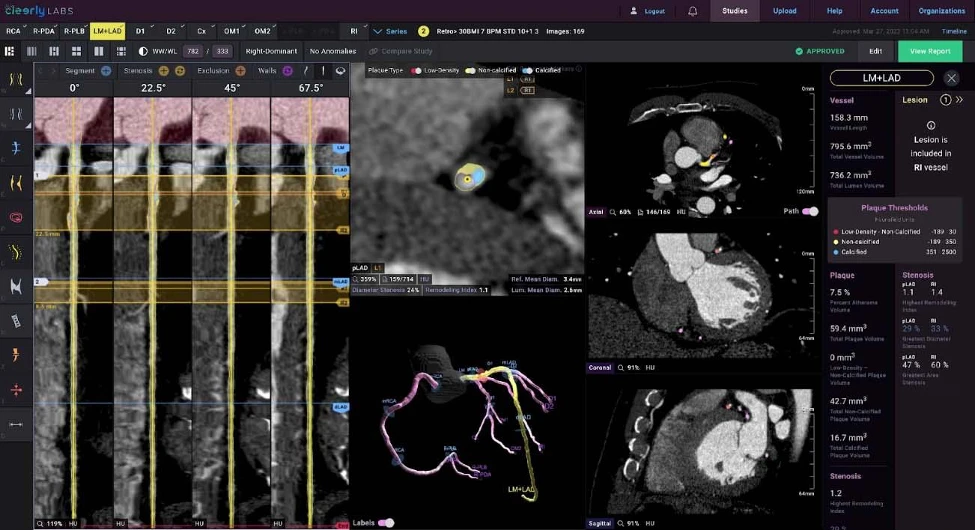

Trong chẩn đoán, AI hỗ trợ phân tích hình ảnh học tim mạch, tự động phát hiện mảng xơ vữa, hẹp mạch hay rối loạn vận động vùng, nâng cao độ chính xác. Công nghệ này còn cho phép cá thể hóa dự báo nguy cơ bằng cách tích hợp dữ liệu từ hồ sơ bệnh án điện tử, thông tin gen và các chỉ dấu sinh học, xây dựng mô hình dự báo cho từng người.

1.png

AI trong CCTA (CT mạch vành), nhân tích mảng xơ vữa, đo mức độ hẹp và hỗ trợ chẩn đoán bệnh mạch vành. Ảnh: BSCC

Kết hợp với thiết bị đeo thông minh, AI có thể theo dõi nhịp tim liên tục, dự báo nguy cơ đột tử hoặc biến cố cấp để can thiệp kịp thời. So với thang điểm truyền thống vốn chỉ dựa trên vài biến số và không cập nhật theo thời gian, AI xử lý hàng trăm yếu tố, liên tục cập nhật từ dữ liệu mới, giúp dự báo chính xác hơn.